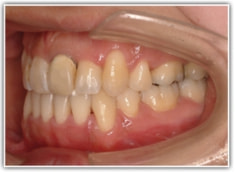

治療前

修復歯、補綴歯もあります。下顎8番が水平埋伏しています。